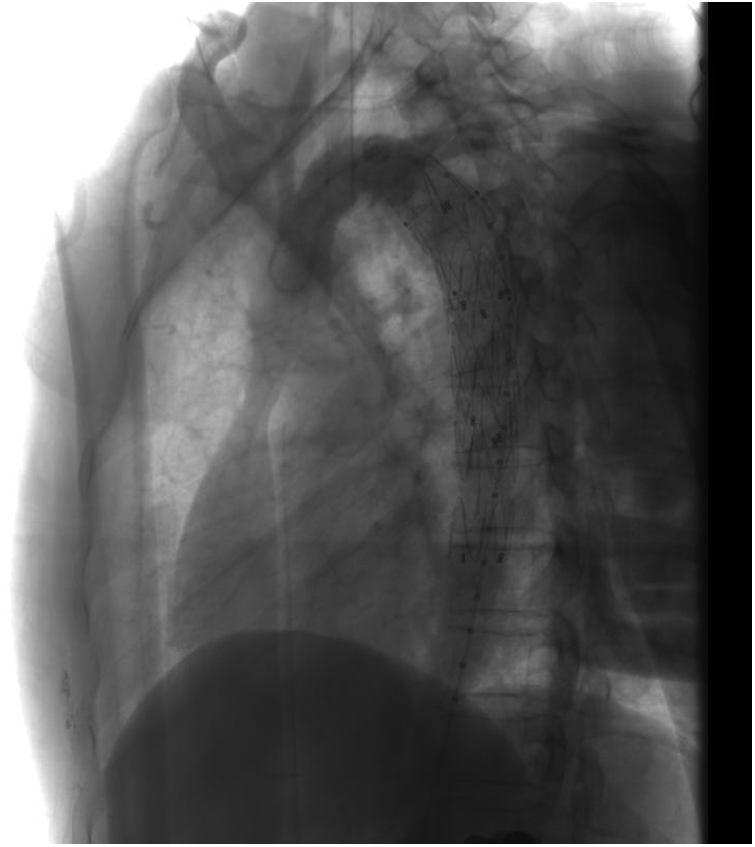

A TEVAR procedure was performed. Considering that the deformity did not cause any clinical symptoms and that the vessel diameter and distance from the proximal anchoring area were sufficient, we decided to anchor the proximal bare stent area to the posterior portion of the dominant arch, and at the meantime, the bare region would not obstruct the non-dominant arch flow, preserving the original aortic arch blood flow (Figure 4). Follow-up CTA scans at one- and six-month post-operation showed that the aortic stent was well-positioned, with no visible primary lesion. The patient reported complete resolution of chest pain and no difficulties with swallowing or breathing (Figures 5, 6).

Figure 4. A TEVAR procedure was performed. The posterior section of the dominant arch was chosen as the proximal anchorage zone, and a stent with proximal bare zone was deployed to maintain blood flow to the distal non-dominant arch and preserve the integrity of the vascular ring.